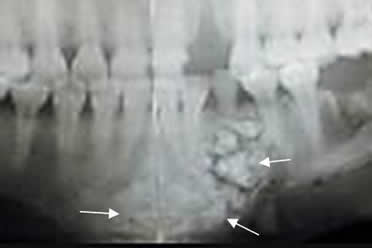

Fig 69. Odontoma.

Ortopantografia. Zona densa y calcificaciones mal definidas, sobre la sínfisis mandibular y que corresponde a odontoma.